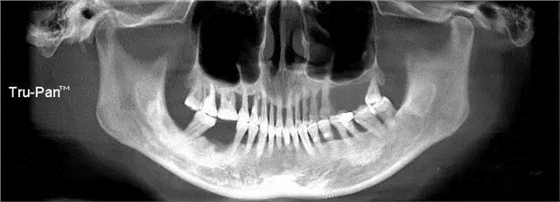

第四圖:上頜竇發(fā)育不足,上頜竇底骨高度充裕,通常頰側(cè)骨壁超級厚,看下圖2.臨床上種植常不需要提升措施。(如需提升,切記頰側(cè)骨厚度過大,開窗的困難性劇增)